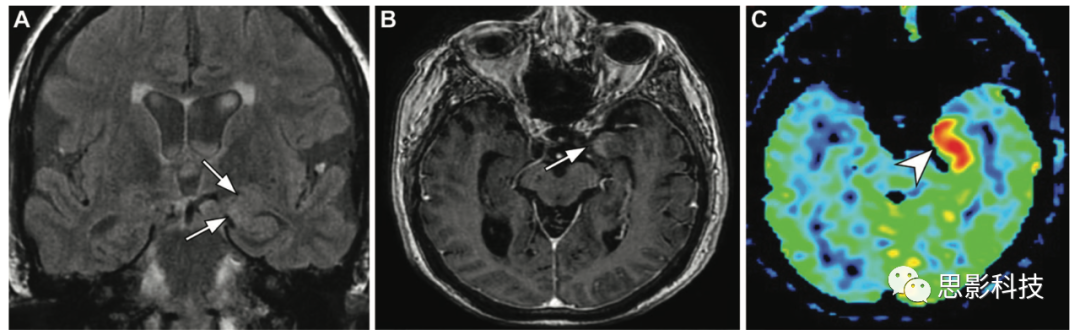

一位54歲患者因嚴(yán)重狹窄導(dǎo)致動(dòng)脈傳輸偽影。(A)右側(cè)頸內(nèi)動(dòng)脈常規(guī)血流空隙消失(箭頭)。(B)ASL MRI顯示動(dòng)脈傳輸偽影(箭頭)導(dǎo)致相應(yīng)的信號(hào)強(qiáng)度增加。

缺血性卒中 在急性缺血性卒中患者,梗死核心代表已經(jīng)梗死的實(shí)質(zhì),表現(xiàn)為擴(kuò)散受限和腦血流減少(4)。缺血半暗帶代表血流灌注較低的組織,有梗死的風(fēng)險(xiǎn)(但如果灌注增加,可能是可以挽救的)。血流灌注-彌散張量的不匹配是指腦血流量低的區(qū)域與代表半暗帶的較小限制區(qū)域之間的差異。已有研究報(bào)道ASLDSC在檢測(cè)半暗帶方面有顯著一致性,但ASL可能會(huì)高估其范圍。由于速度選擇性ASL以血流速度為基礎(chǔ),最大限度地減少了ASL MRI傳輸時(shí)間延遲的影響,因此可以改善緩慢和側(cè)支循環(huán)條件下CBF評(píng)估。梗死核心和半暗帶的確定有助于管理和預(yù)測(cè)臨床結(jié)果。最近一項(xiàng)研究表明,急性卒中患者的ASL圖像能夠提供比單獨(dú)使用彌散加權(quán)MRI更多的信息,ASL對(duì)評(píng)估陰性急性缺血性卒中的預(yù)測(cè)價(jià)值為94%。Belani等人指出,對(duì)24.5%的急性腦卒中患者和7.4%的非急性腦卒中患者中,將ASL納入常規(guī)腦MRI檢查可以提供更多信息。

12 一例40歲女性高級(jí)別膠質(zhì)瘤,右側(cè)偏癱15天。(AB)軸位FLAIR圖像(A)顯示左側(cè)額葉病變(箭頭),ASL(B)顯示高信號(hào)(箭頭)。(C)3個(gè)月后獲得的軸位增強(qiáng)后T1加權(quán)像顯示較大的壞死性病變(箭頭),周圍有不規(guī)則強(qiáng)化,與膠質(zhì)母細(xì)胞瘤相關(guān)。

13 一例69歲男性腎功能衰竭患者發(fā)生中樞神經(jīng)系統(tǒng)淋巴瘤,表現(xiàn)為嗜睡、左側(cè)偏癱和震顫。(A)軸位彌散加權(quán)成像顯示右側(cè)顳葉軸內(nèi)浸潤性病變,彌散均勻(箭頭),腫塊效應(yīng)伴右側(cè)腦室體部受壓,中線結(jié)構(gòu)輕微左移。

(B)ASL MRI顯示右側(cè)顳葉(箭頭)高灌注。